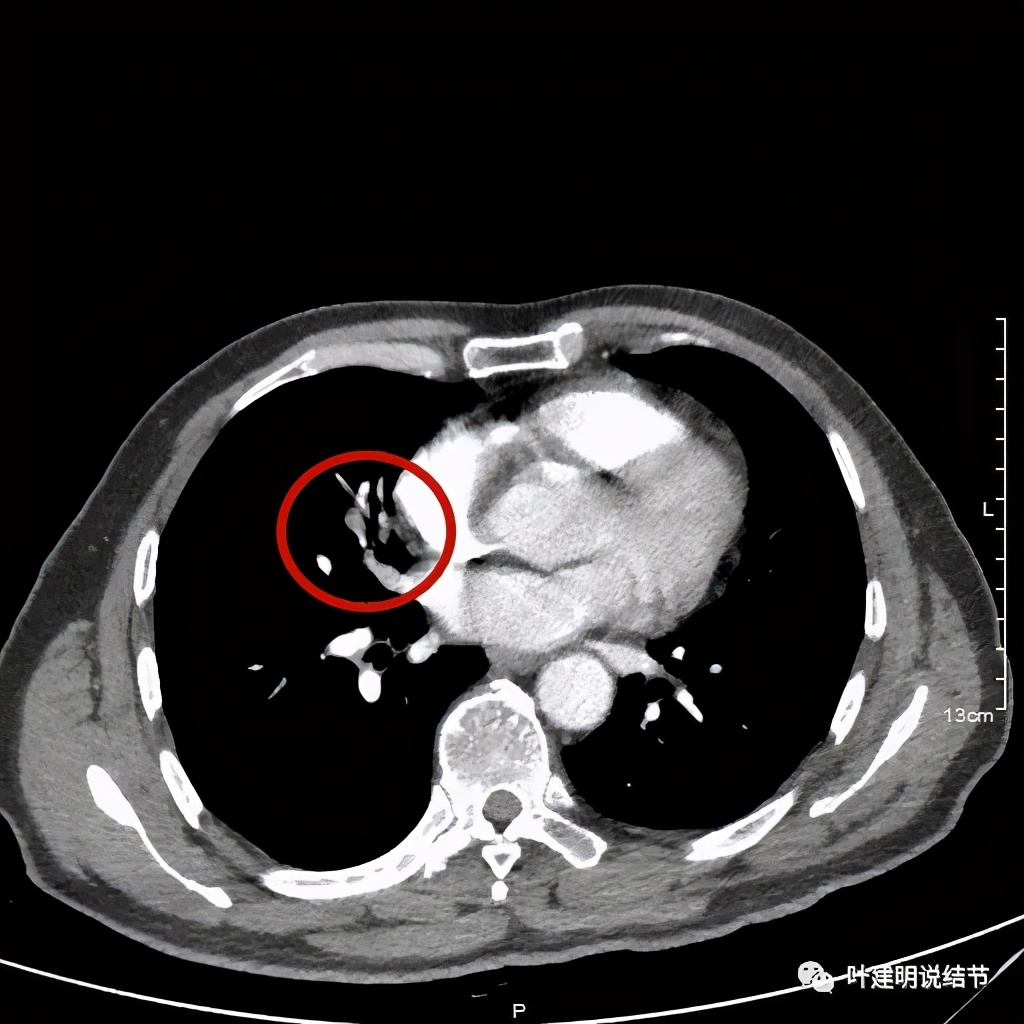

上图示病灶实性,且粉色箭头所示处边缘不平整,似细毛刺征(不太典型),蓝色箭头示像支气管截断(肿瘤堵塞的样子,但后文中有气管镜下未见异常,那么可能是角度的关系)